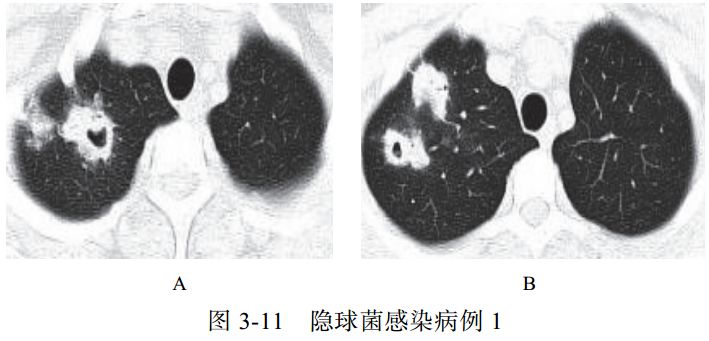

(二)隐球菌感染

影像学表现:

(1)呈单发或多发斑片 、 类 圆形 或结 节 影, 多位 于 胸膜下(图 3-11)。

(2)可出现小空洞、晕征,有时呈炎性肿块改变(图 3-12)。

(3)肺门及纵隔淋巴结一般无肿大。

(4)病情进展缓慢。

图片